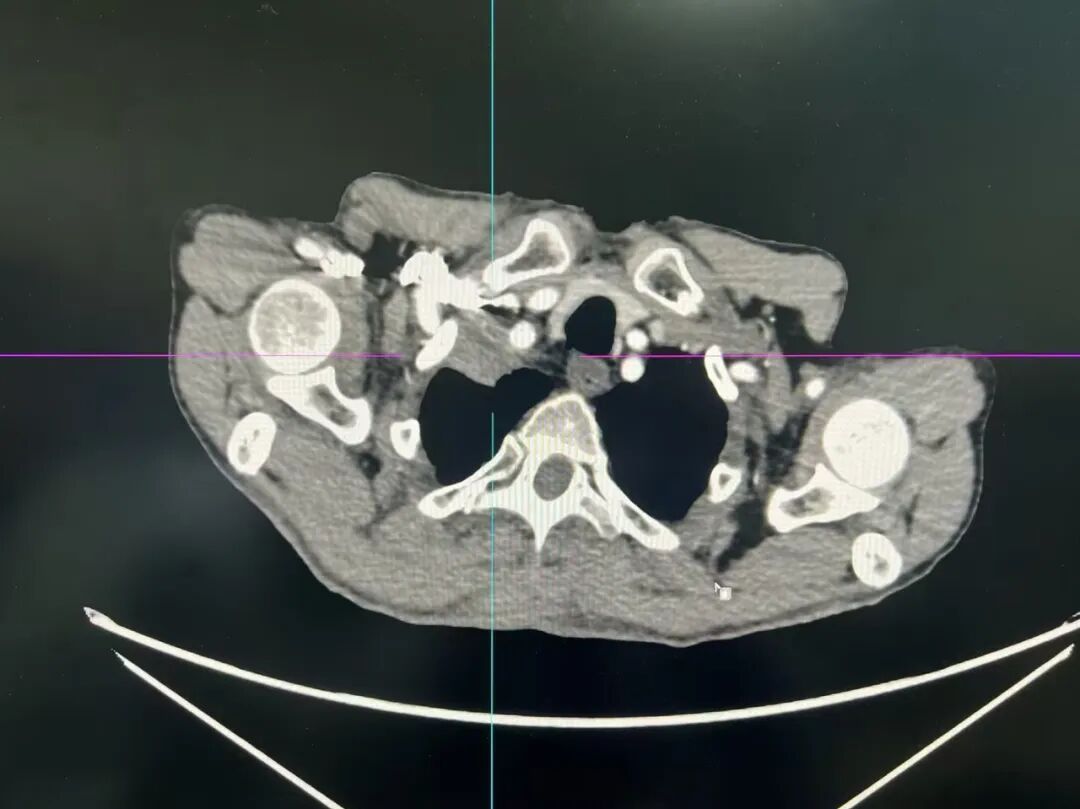

68岁的患者陈先生,被反复咳嗽、咳痰、喘促等症状困扰已逾3年,近两个月病情突然加重,稍作活动便呼吸困难。在我院门诊进行CT检查后,报告提示其右肺上叶尖段存在占位灶,不排除肺癌可能,随即以“慢性阻塞性肺病伴有急性下呼吸道感染、肺占位性病变”收住肿瘤科。进一步的增强CT检查,更指向该占位多为恶性,且高度怀疑是肺上沟癌——明确病理诊断,成为摆在医疗团队面前的首要任务。

然而,患者肺部肿物位置特殊,“藏”在肺尖深处,被多层骨性结构牢牢包裹,周边更是紧邻锁骨下动静脉、头臂干等重要大血管。常规CT引导下,医生反复推演都无法找到安全的穿刺路径;同时,患者右侧腋窝、锁骨上下窝的肿大淋巴结也让病情更加复杂。

CT影像图